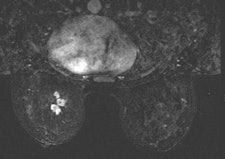

Among the modalities, MRI has carved out a large and growing role in breast cancer management, but even this imaging superstar should be considered an adjunctive -- rather than primary -- modality for achieving optimal care, she said.

According to the 2013 American College of Radiology (ACR) guidelines, breast MRI should be performed for screening high-risk patients, as well as those with a new breast malignancy, following a 2007 report in the New England Journal of Medicine on MRI's ability to find cancer in the contralateral breast. It should also be used to screen patients with breast augmentation, which presents difficulties such as mammographically occult regions, or cancer tracking the contour of the implant, Shaheen said.

For confirmed cancers, MRI can be used to assess the extent of disease such as ductal carcinoma in situ, for additional evaluation of imaging or clinical findings, and for problem-solving.

On the other hand, MRI is not suitable for screening the general population. It may turn up false positives or findings that are not clinically significant.

MRI may change patient management, but it is not a primary screening modality, Shaheen said.

"Breast MRI is not a substitute whatsoever for other modalities or biopsy," she said.